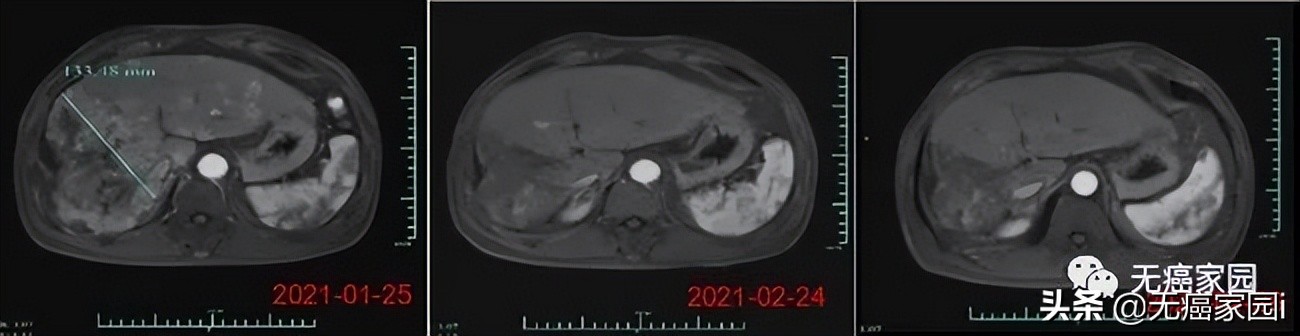

在数据截止时,受试者007的部分缓解时间6个月, 其肿瘤体积在细胞治疗输注后1个月减少了80%以上。 (截至2021年6月,该受试者已超过8个月的疾病控制,随访仍在进行中)。受试者012是1例弥漫型、巨块型晚期肝癌患者,曾接受过12次以上的TACE治疗、放疗及靶向治疗,不幸的是均无效,随后参与本研究。

在输注CAR-T细胞后的第28天,受试者MRI结果显示最大肿瘤直径从最初的133毫米减少至9毫米,缩小超过93%。目前,该受试者正在接受CAR-T细胞输注后第3个月的评估,MRI扫描显示此肿瘤几乎消失。 此外,甲胎蛋白(AFP,原发性肝癌的特定肿瘤标志物)水平从基线值 >80,000/ng/ml 下降到第1个月的1148.9ng/ml,并在第3个月下降到746.7ng/ml输注(正常范围<40ng/ml),证明Ori-CAR-001在晚期肝癌患者中具有显著的初步疗效。

受试者012的MRI结果示意图